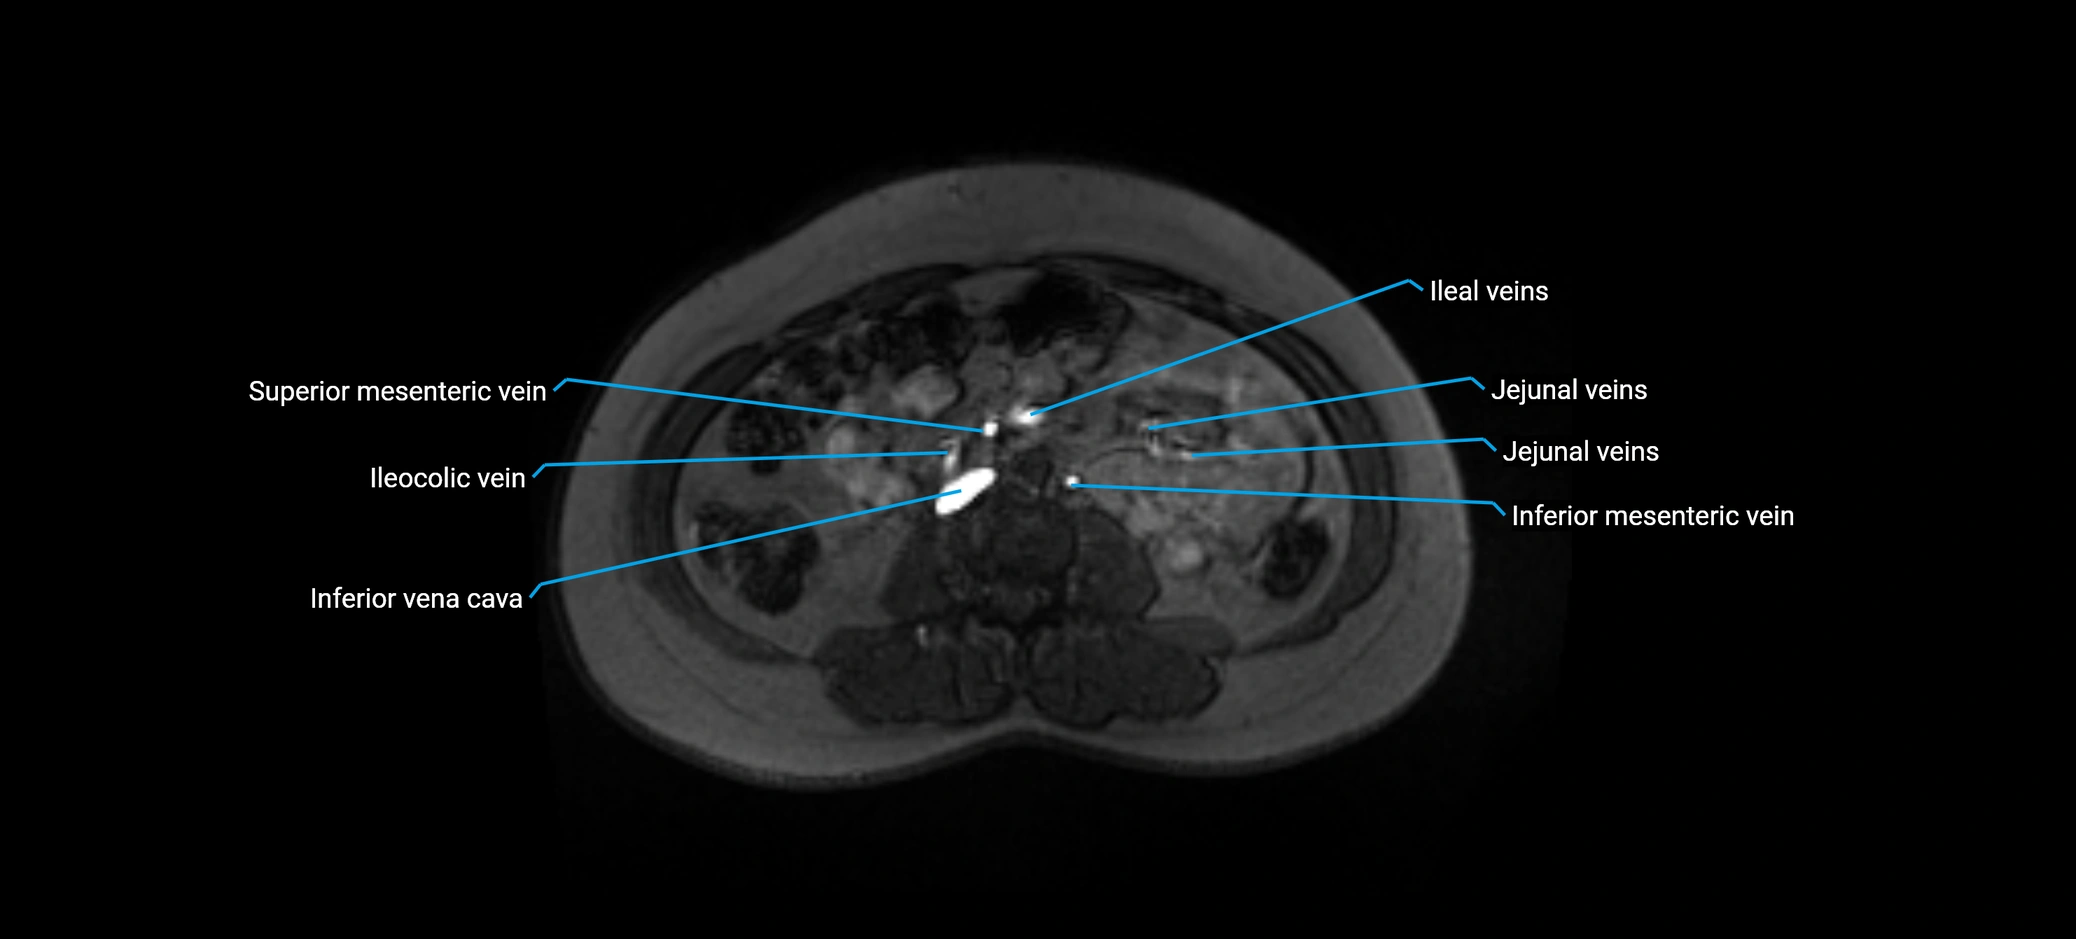

Distribution (Hepatic Segments):

• Segment V (anteroinferior right lobe)

• Segment VIII (anterosuperior right lobe)

MRI image

image